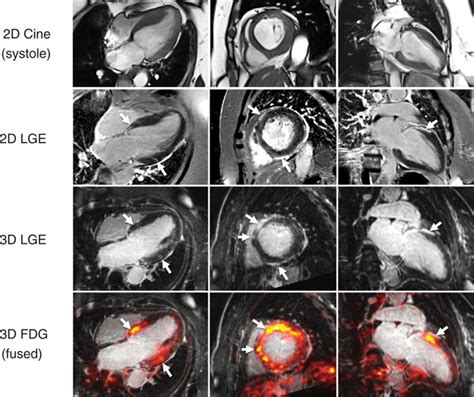

• Cine MRI: This sequence captures moving images of the heart, allowing cardiologists to assess heart function and blood flow.

• T1-weighted and T2-weighted images: These sequences help identify tissue characteristics, such as inflammation or scarring.

• Contrast-enhanced MRI: By injecting a contrast agent, cardiologists can enhance the visibility of certain structures and detect abnormalities more effectively.

• 4D Flow MRI: This technique provides dynamic information about blood flow within the heart and great vessels, offering a more comprehensive understanding of cardiovascular physiology.

• Hybrid Imaging: Combining MRI with other imaging modalities, such as PET (positron emission tomography), can provide even more detailed information about heart function and metabolism.